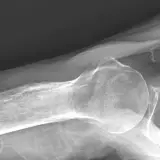

Over 2,100 interactive radiology cases, curated by radiologists for your level of training. Scroll, window, and view cases full screen — just like on PACS. Click linked findings in each writeup to jump straight to them on the image. Cases include sample reports, a focused discussion section, original illustrations, and videos.

Casos totalmente interativos com as ferramentas que você espera em um PACS — rolagem, ajuste de janela, zoom, movimentação, medidas, ROIs e modo de tela cheia.

Anotações detalhadas destacam os achados principais diretamente nos casos. Clique nos achados vinculados nas descrições dos casos para ir ao local exato no exame.

Role, movimente, ajuste janela e amplie como em uma estação PACS do trabalho